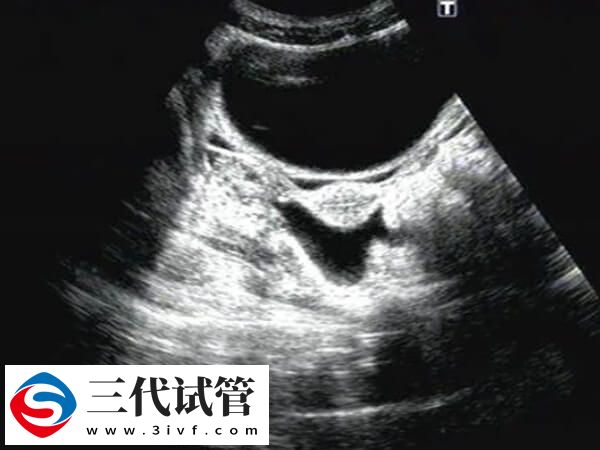

试管囊胚移植40天宫腔有积液的干净时间不可一概而论,还需要根据实际情况进行判断,毕竟每个患者身体情况不同多样积液消失时间也会有差异,建议出现宫腔积液的患者,应该定期进行超声检查,监测积液的变化,然后根据医生的建议进行适当的保胎措施。

鲜胚移植后40天有子宫积液会增加流产风险,但大部分超声提示的少量积液在没有明显阴道出血的情况下,并不一定意味着会发生流产,所以患者无需过度紧张,至于患者在鲜胚移植后40天发现子宫积液,要怎样才能排出,对此感兴趣的可参考下列内容: